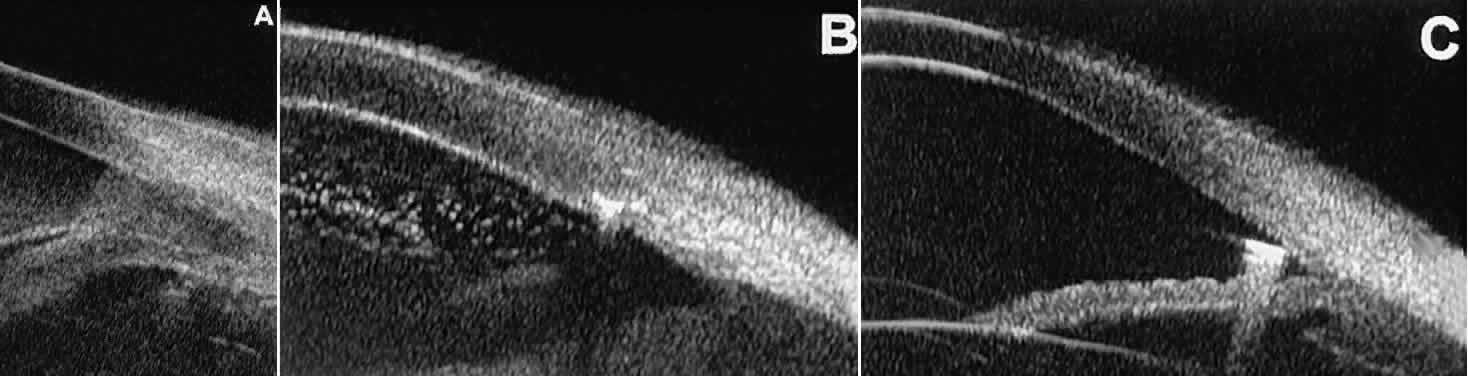

In open-angle glaucoma, UBM can be used to measure the anterior chamber angle in degrees, to assess the configuration of the peripheral iris, and to evaluate the trabecular meshwork (Fig. 9).2,4 The angle configuration can be graded and compared with gonioscopic findings. In certain patients with open-angle glaucoma, UBM can provide information that may be of some diagnostic value (Fig. 10). For example, in pigment dispersion syndrome (see Fig. 10A),6 UBM typically reveals posterior bowing of the peripheral iris (“q” configuration of peripheral iris by Spaeth classification5). In plateau iris syndrome (see Fig. 10B),7 UBM usually reveals abnormally steep anterior angulation of the peripheral iris (“s”configuration of peripheral iris by Spaeth classification5), insertion of the iris from the anterior ciliary body, and retroiridic projection of the ciliary processes. In eyes with peripheral anterior synechiae (see Fig. 10C and D), UBM can reveal the extent of iridocorneal adhesion even if the cornea is hazy or opaque.

Fig. 9. Angle configuration in eyes with open-angle glaucoma. A. Wide open angle with flat iris plane (D40r configuration by Spaeth gonioscopic grading system). B. Moderately wide angle with anteriorly bowed iris plane (C30r by Spaeth gonioscopic grading system).

Fig. 10. UBM features of special glaucoma cases. A. Pigment dispersion syndrome with posterior bowing of peripheral iris (“q” configuration by Spaeth gonioscopic grading system). B. Plateau iris syndrome with origin of iris from anterior surface of ciliary processes behind peripheral iris, slitlike narrowing of peripheral angle, and abrupt transition from steep peripheral iris to flat iris midzone. C. Broad peripheral anterior synechia with posterior bowing of nonadherent iris. D. Peripheral anterior synechia with aqueous-filled slit between site of iridocorneal adhesion and iris root after cataract extraction with implantation of posterior-chamber IOL.

In eyes with a narrow angle, UBM shows the extent of angle closure, reveals the depth of the anterior and posterior chambers, and identifies pathologic processes pushing the lens and iris forward (Fig. 11).2–4,8 UBM has been able to differentiate between primary angle closure (i.e., cases of angle closure without additional pathology responsible for the anterior lens-iris displacement [see Fig. 11A] and secondary angle closure due to processes such as lens swelling and dislocation (see Fig. 11B), massive hemorrhagic retinal detachment pushing the lens and iris anteriorly (see Fig. 11C), and multiple neuroepithelial cysts of the iridociliary sulcus (see Fig. 11D).

Fig. 11. Angle configuration in eyes with angle-closure glaucoma. A. Primary angle-closure glaucoma with anterior displacement of lens and iris. B. Angle closure secondary to swollen, cataractous lens (phakomorphic angle closure). C. Angle closure secondary to massive hemorrhagic retinal detachment; the subretinal blood is evident in the lower right corner of the photograph. D. Angle closure secondary to multiple peripheral iris cysts.